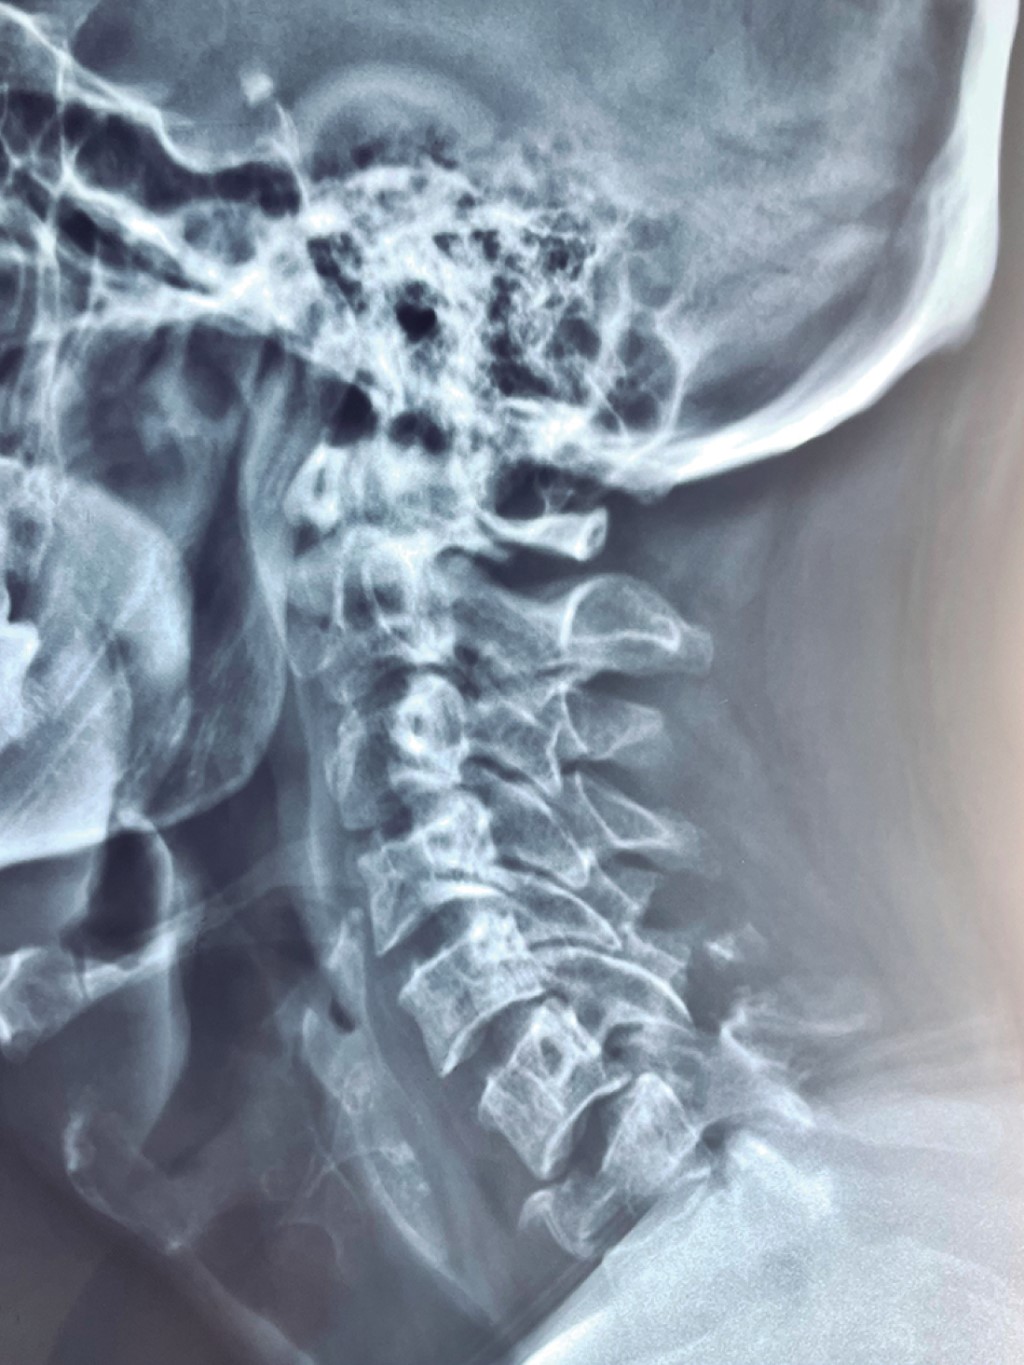

Se presenta el caso de un paciente masculino de 33 años de edad, sin comorbilidades, que acude al servicio de urgencias por presentar cervicalgia de dos semanas de evolución posterior a un accidente en motocicleta. Las radiografías iniciales tomadas en el hospital de primera atención no fueron valorables para diagnóstico; se toman radiografías y tomografía axial computarizada (TAC) de columna cervical (Figuras 1, 2 y 3), diagnosticando fractura de C1 y C7 donde se observa fractura por compresión de C7 AO B2 y C1 con fractura de arco anterior y posterior izquierdo con desplazamiento coronal > 7 mm de la masa lateral izquierda. En la resonancia magnética T2 axial, se observa lesión del ligamento transverso. En resonancia magnética simple se observa fractura de cuerpo vertebral de C7, con compromiso de conducto raquídeo